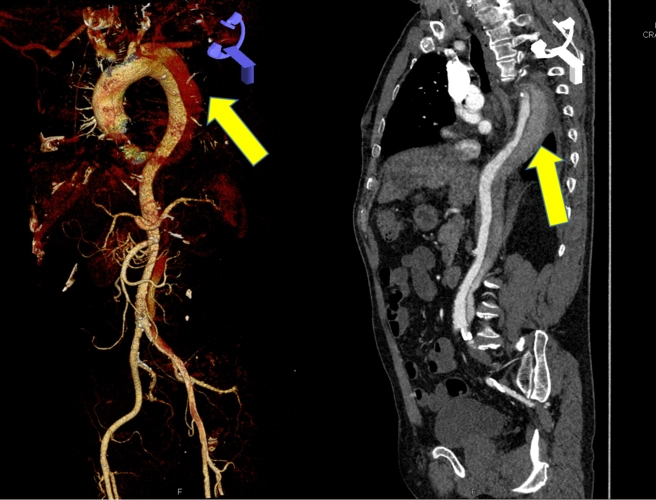

马凡综合征合并自发性孤立性腹主动脉夹层一例

以腹痛为首发症状的主动脉夹层1例